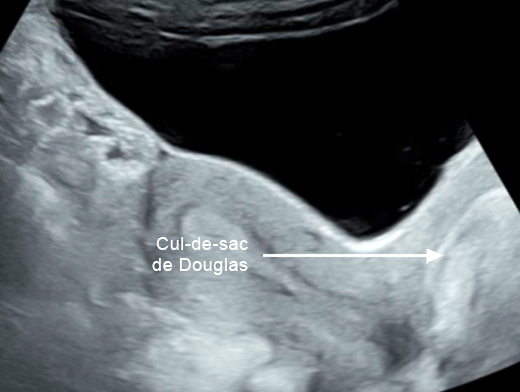

Mme G. est finalement césarisée sous anesthésie générale sans complication. Lors de l’hystérotomie, le liquide amniotique est sanglant avec de nombreux caillots. Les pertes sanguines sont estimées à 1 500 mL. L’équipe d’anesthésie a administré en peropératoire un culot de globules rouges et un plasma frais congelé (PFC), ainsi que de l’acide tranexamique. L’utérus est tonique en fin d’intervention. Au cours de la surveillance en salle de surveillance post-interventionnelle (SSPI), à quatre heures postopératoires, Mme G. a une barre épigastrique résistante aux antalgiques de palier 3. Les constantes sont les suivantes : pression artérielle = 190/110 mmHg ; fréquence cardiaque = 120 bpm ; saturation en oxygène = 99 % en air ambiant. Compte tenu de la tachycardie, vous réalisez une échographie transabdominale dont les images sont les suivantes. Figure 2a (Rodolphe Matias de Sousa, La Revue du Praticien)Figure 2b (Rodolphe Matias de Sousa, La Revue du Praticien)Figure 2c (Rodolphe Matias de Sousa, La Revue du Praticien) Vous décidez d’avancer le prochain bilan biologique et récupérez les résultats suivants : hémoglobine = 8,7 g/dL ; plaquettes = 40 G/L ; TP = 65 % ; TCA = 1,02 ; fibrinogène = 2 g/L ; haptoglobine indosable ; ASAT = 260 UI/L ; ALAT = 240 UI/L.

Concernant l’hématome sous-capsulaire du foie : Tableau 3 (Rodolphe Matias de Sousa, La Revue du Praticien) Concernant l’échographie transabdominale à la recherche d’un hémopéritoine :on regarde deux espaces, le cul-de-sac de Douglas entre l’utérus et le rectum, et l’espace de Morrison entre le foie et le rein. Figure 3a (Rodolphe Matias de Sousa, La Revue du Praticien)Figure 3b (Rodolphe Matias de Sousa, La Revue du Praticien)Figure 3c (Rodolphe Matias de Sousa, La Revue du Praticien) Pour rappel, concernant l’échographie en gynécologie : Figure 4a (Rodolphe Matias de Sousa, La Revue du Praticien)Figure 4b (Rodolphe Matias de Sousa, La Revue du Praticien)Figure 4c (Rodolphe Matias de Sousa, La Revue du Praticien)Figure 4d (Rodolphe Matias de Sousa, La Revue du Praticien)Figure 4e (Rodolphe Matias de Sousa, La Revue du Praticien)Figure 4f (Rodolphe Matias de Sousa, La Revue du Praticien)Figure 4g (Rodolphe Matias de Sousa, La Revue du Praticien)Figure 4h (Rodolphe Matias de Sousa, La Revue du Praticien)Figure 4i (Rodolphe Matias de Sousa, La Revue du Praticien)